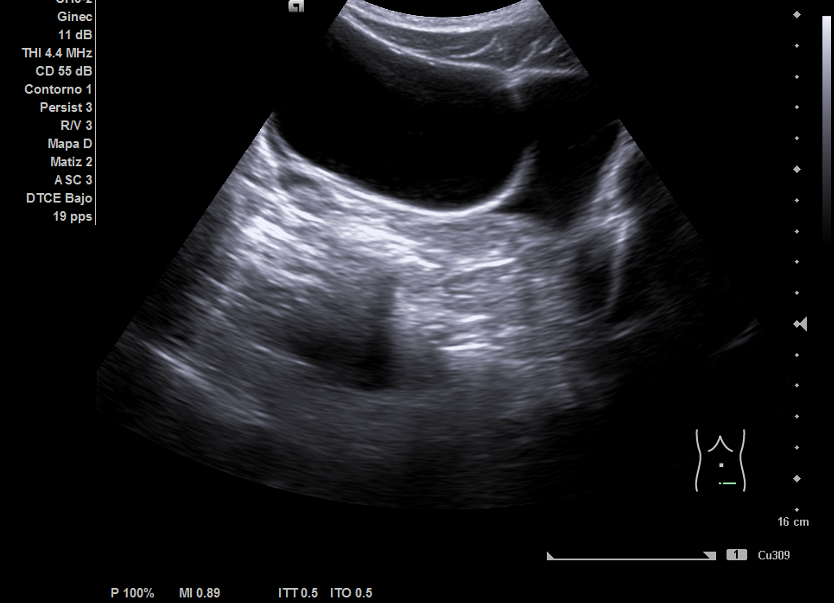

Ecografía abdominal: hígado y vesícula sin alteraciones. Riñones de ecoestructura normales. Útero de características normales. Se apreció imagen anecoica de 7x7 cm que parecía depender de ovario derecho.

En Ginecología se realizó ecografía ginecológica transrectal en la que se confirmó quiste ovárico derecho de unos 79 mm de contenido líquido sin tabiques ni papilas. Con el diagnóstico de crisis de pseudotorsión ovárica se programó para cistectomía de ovario derecho. La anatomía patológica confirmó la presencia de un cistoadenoma mucinoso.